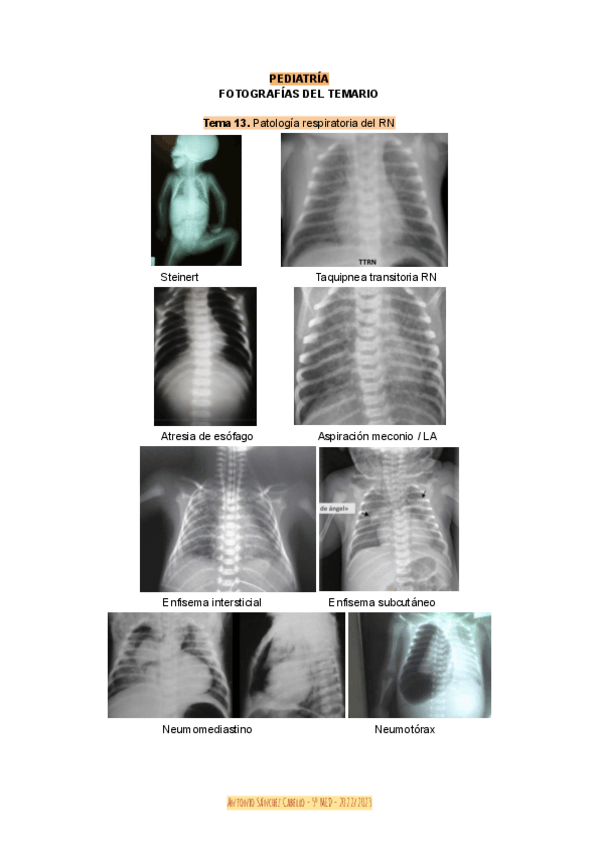

He publicado nuevos apuntes de 5º PEDIATRÍA Y CIRUGÍA PEDIÁTRICA I: imagenes-pedia.pdf

He publicado nuevos apuntes de 5º PEDIATRÍA Y CIRUGÍA PEDIÁTRICA I: FOTOS-PEDIA-I.pdf

He publicado nuevos apuntes de 5º PEDIATRÍA Y CIRUGÍA PEDIÁTRICA I: Fotografias-Pediatria.pdf